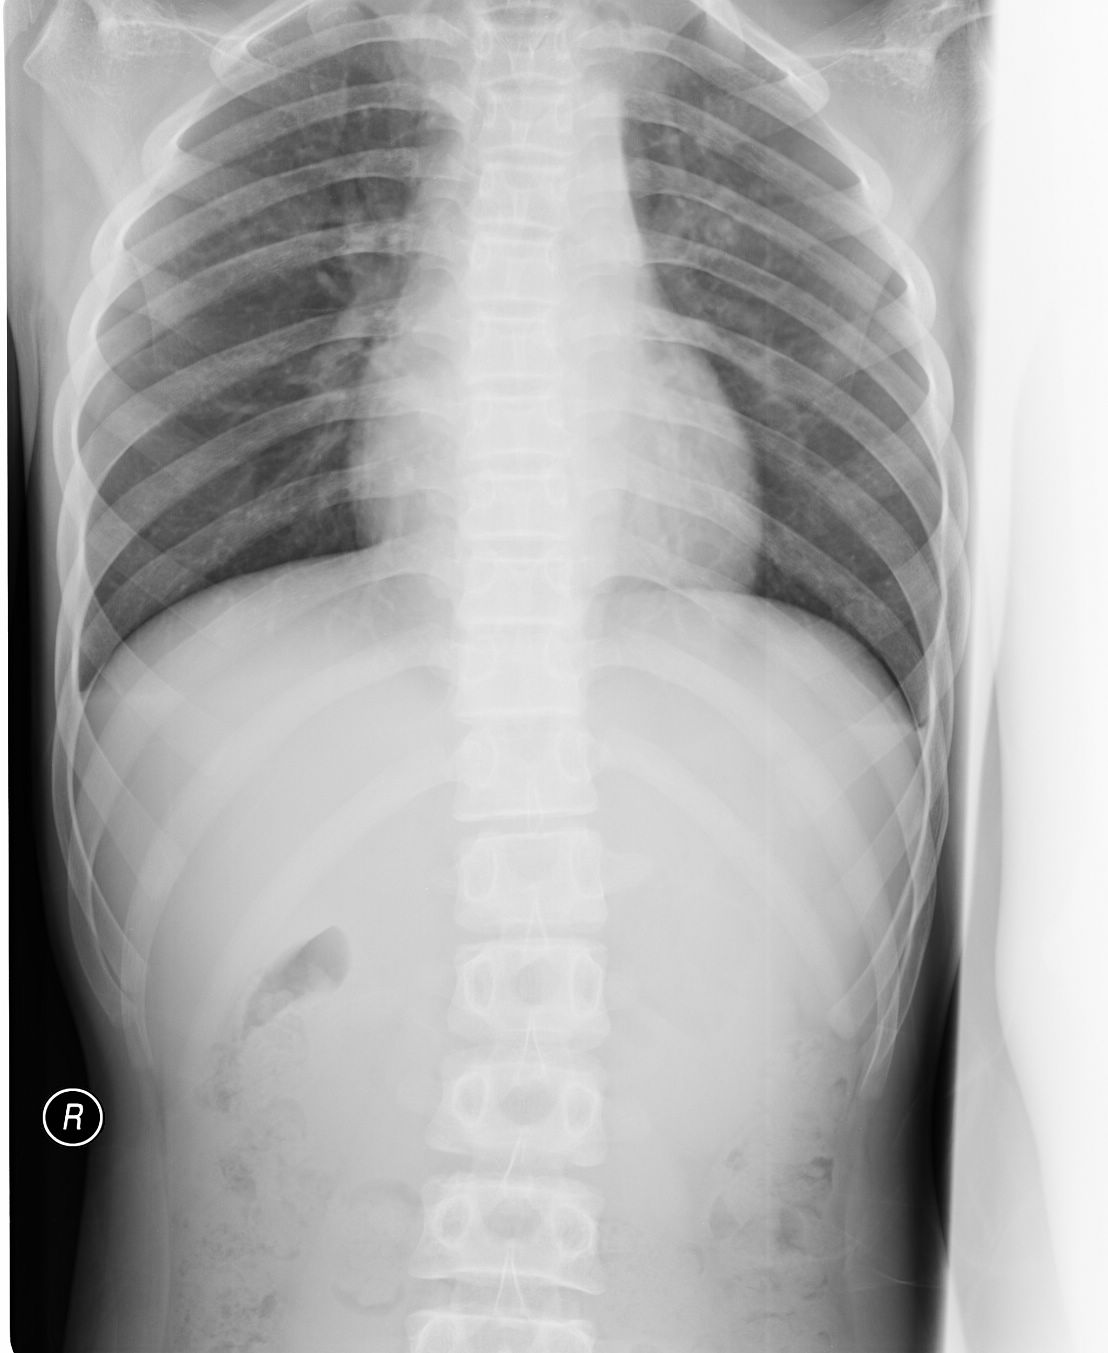

以下是引用黑白光影在2009-8-27 14:24:00的发言:[br]侧位显示胸腰段t12、l1、l2与其它椎体发育形态不一致,支持楼主考虑,建议作进一步检查确定。

以下是引用胡宇在2009-8-27 23:02:00的发言:[br][br] 骨质未见明显异常,学龄患者,要考虑长期伏案学习坐姿不正,继发肌肉及脊柱改变。带背背佳矫形试一试!t12、l1、l2椎体轻度楔变为应力性改变,很常见,不支持青年性驼背(椎体骺板骨软骨炎)。 [br]

以下是引用zxl51642在2009-8-27 12:04:00的发言:[br]骨质未见明显异常,学龄患者,要考虑长期伏案学习坐姿不正,继发肌肉及脊柱改变。带背背佳矫形试一试!t12、l1、l2椎体轻度楔变为应力性改变,很常见,不支持青年性驼背(椎体骺板骨软骨炎)。